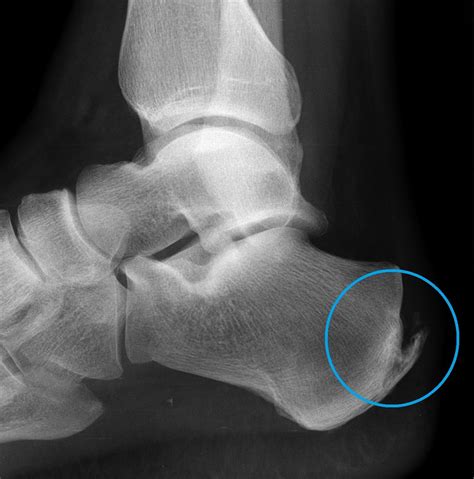

Visual aids can be incredibly helpful in understanding the condition. Below are some foot spurs pictures that illustrate the appearance and location of heel spurs:

This image shows a typical heel spur, highlighting the bony protrusion on the underside of the heel bone. The spur is often associated with plantar fasciitis, where the plantar fascia becomes inflamed and thickened.

Another example of a heel spur, this image provides a clearer view of the bony growth and its location on the heel. The spur can vary in size and shape, depending on the severity of the condition.